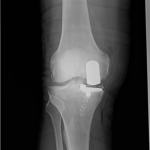

PRACHATICE – Na ortopedickém oddělení Nemocnice Prachatice byl minulý týden proveden unikátní výkon – implantace oboustranné částečné náhrady kolenního kloubu. Jde o málo frekventovaný typ operace, který se provádí jen na menším počtu ortoepedických pracovišť v České republice.

Unikondylární náhrada představuje šetrnější variantu totální endoprotézy – nahrazuje pouze poškozenou část kolenního kloubu, zatímco zbytek zůstává zachován. Aby pacient z operace skutečně profitoval, je nutné splnění indikačních kritérií, která lze shrnout do několika bodů: artrotické postižení jedné poloviny kloubu a dobrý stav té druhé, funkční vazy, dobrý rozsah pohybu, nepřítomnost výrazné deformity.

S oboustrannými implantacemi totálních endoprotéz mají v prachatické nemocnici již několikaleté zkušenosti. Nyní však poprvé provedli dvojitou operaci částečné náhrady. Zásadní je přitom nejen zvládnutá operační technika, ale i souhra celého týmu, díky které je pacient schopen se již v prvních hodinách po výkonu postavit, operované klouby zatížit a relativně bezbolestně zvládat rehabilitaci.